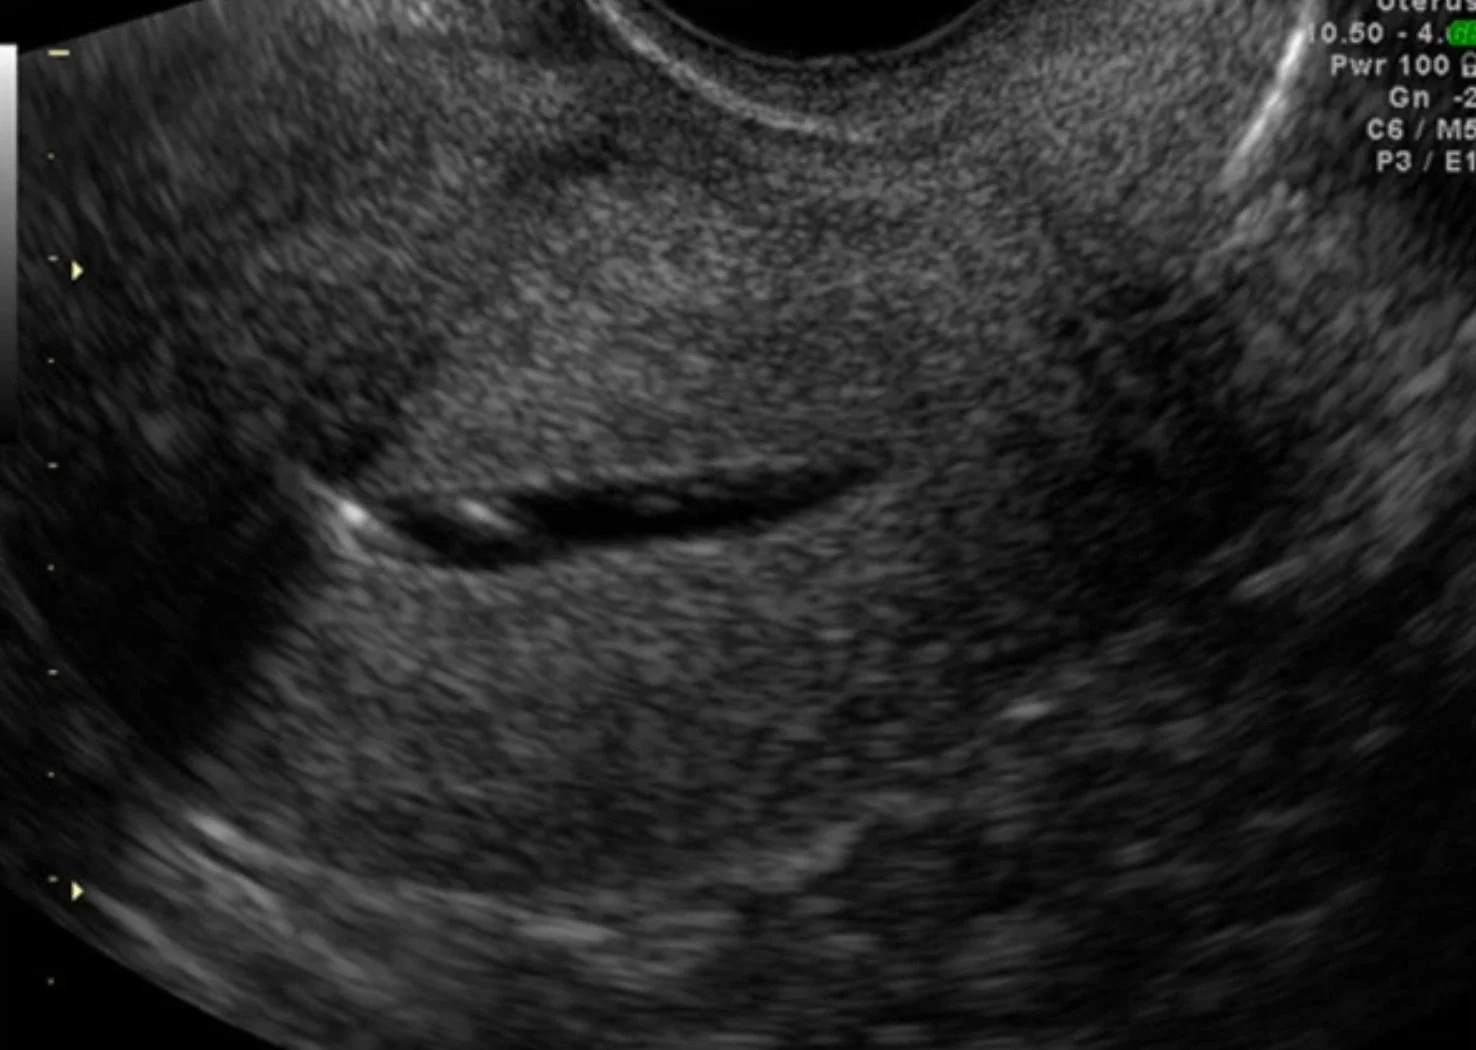

HyCoSy showing a normal uterus shape, the fallopian tubes open (black & white arrows) and fluid beneath the uterus, indicating open tubes and water flow into the abdomen

During a HyCoSy, a fizzy salt water (saline) solution is introduced into your uterus in a similar way to the dye discussed above using a speculum. This solution is tracked as it moves through your fallopian tubes with the help of a soft plastic tube, or catheter, placed inside your cervix, and an internal ultrasound. The bubble water creates bright echoes, allowing your fallopian tubes to be clearly seen and reveal any blockages. This image is further enhanced with colour Doppler (blood flow) imaging.

What does the HyCoSy involve?